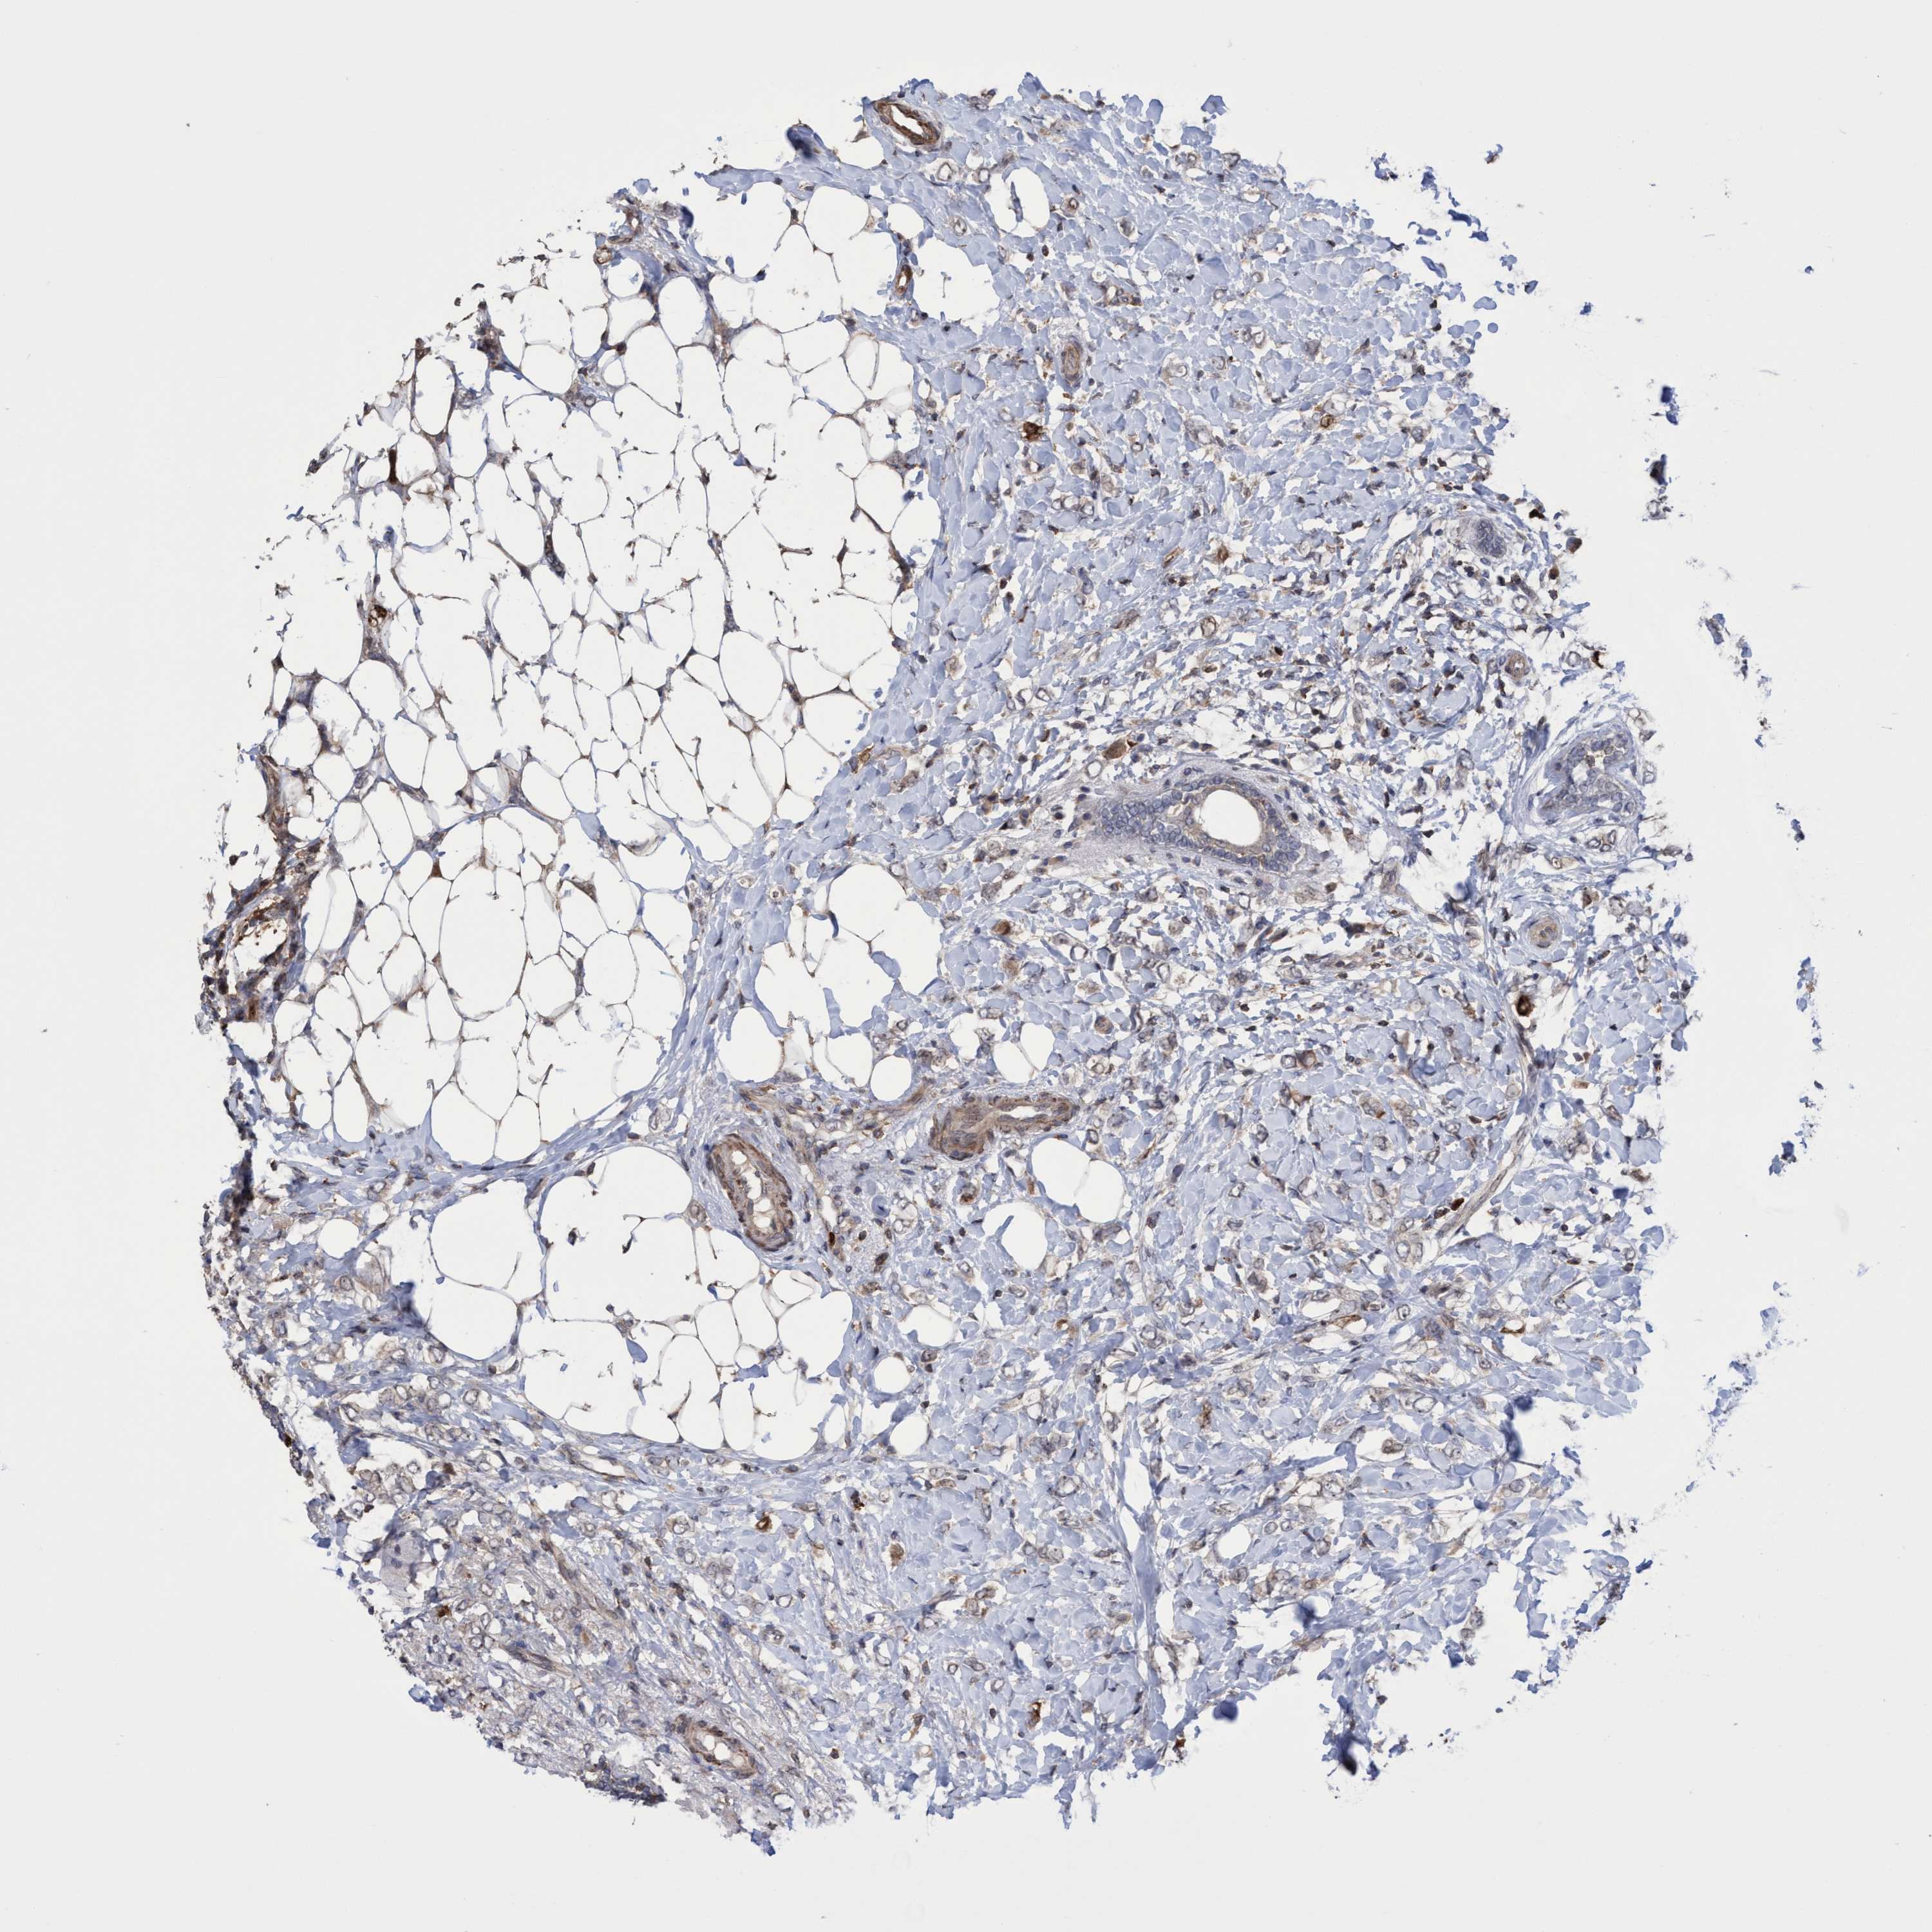

CANCER BREAST CANCER Show tissue menu

BRCA TCGA BRCA VALIDATION PROTEIN EXPRESSION